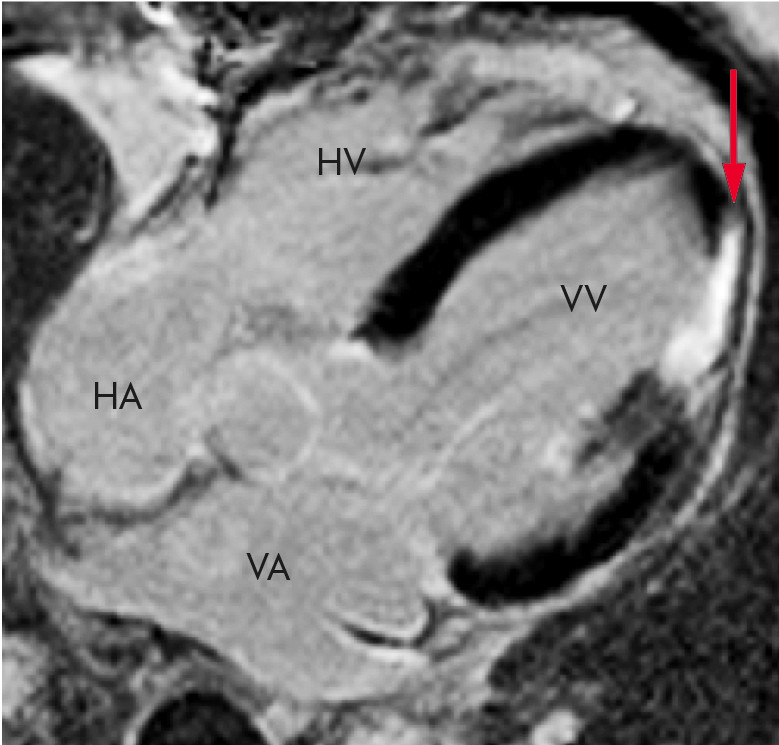

Ved erstatningsfibrose kan man påvise kvalitative forskjeller i senopptak av gadoliniumholdige kontrastmidler (10, 18). Etter gjennomgått hjerteinfarkt ses økt senopptak forenlig med erstatningsfibrose (figur 5). Ved ikke-iskemiske hjertemuskelsykdommer vil senopptak være assosiert med økt hypertrofi og forverret prognose ved flere tilstander (23, 24). Det er viktig å være klar over at senopptaksmetoden er uegnet for fibrosevurdering ved diffus fibrose med homogent myokard (15, 25).